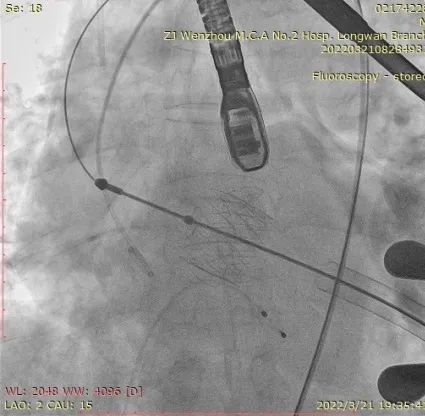

4.患者术中造影角度LAO:1°,CAU:15°。

术中DSA参考投照角度:LAO 1°,Caudal 15°

经股静脉置入临时起搏器,并经股动脉植入6F猪尾管。行第五肋间小切口并在心尖部缝制荷包。穿刺心尖后进泥鳅导丝过主动脉瓣经过主动脉弓到达降主动脉膈肌水平。单弯管交换硬导丝后,用16F扩张鞘预扩心尖穿刺处,后将 J-Valve瓣膜(27mm)装入输送器并经心尖穿刺处推送至主动脉根部,释放定位件,并微调角度使其入窦,后完全释放瓣膜,撤出输送器。通过DSA和TEE观察人工瓣膜膨胀后金属支架的形态、位置,有无瓣周漏。撤出导丝,收紧心尖处荷包线并打结,后鱼精蛋白中和肝素,彻底止血,逐层关胸,封皮,拔出股动脉鞘并在股动脉穿刺处压迫止血。手术过程顺利,患者生命体征平稳。

瓣膜释放泥鳅导丝和单弯管过弓

加硬导丝建立轨道

介入器过瓣环平面

释放定位件

瓣膜入座

瓣膜自膨

松开锁丝,撤出输送器

DSA和TEE显示无瓣周漏,瓣膜位置、形态良好